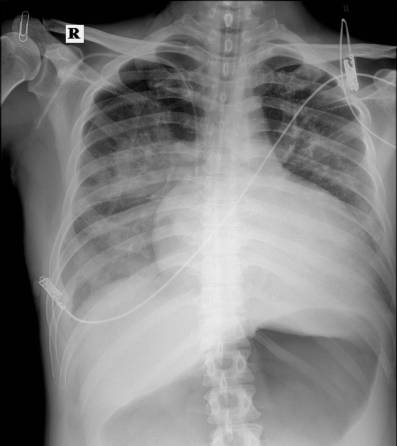

2015年9月22日